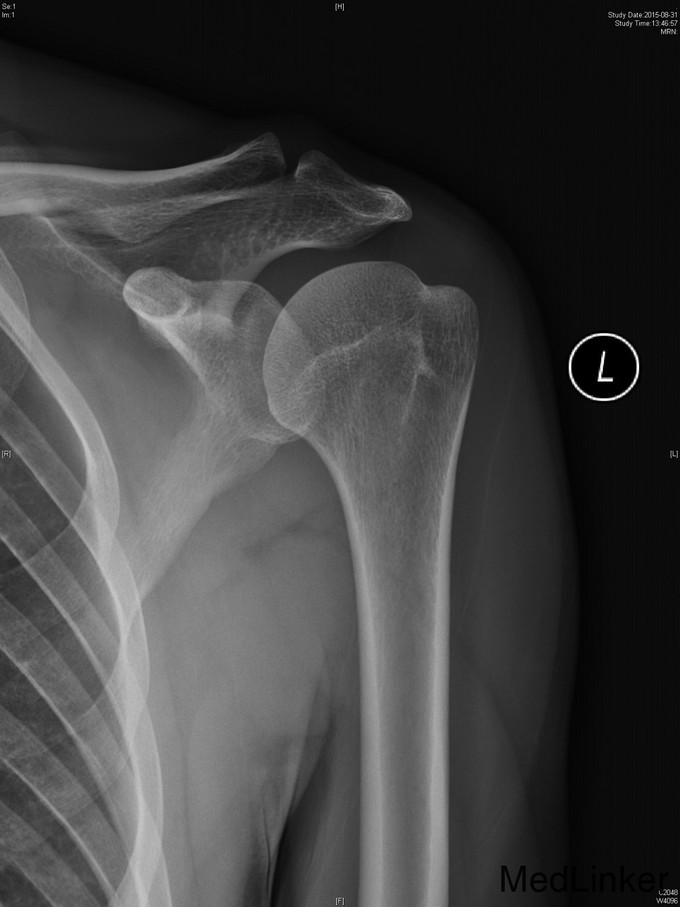

主诉:左肩扭伤后疼痛不适伴弹响10余年,加重3月。 现病史:患者10余年前扭伤左肩关节后出现疼痛不适等症状,伴活动时弹响,以运动时明显。患者当时未重视,未就诊。10余年来患者左肩疼痛不适症状反复发作,曾至外院行局部理疗、小针刀等保守治疗,效果不佳。3月前患者再次扭伤左肩,当即感觉左肩症状加重。来我院就诊,我院行MRI检查示:左肩盂唇信号异常及肱二头肌长头肌腱信号异常。

右上肢、双下肢肌力及活动度正常。左肩关节周围肌肉萎缩,左肩前方压痛(+),无明显肿胀。左肩关节活动度尚正常,Hawking征(-),Neer征(+-),Jobes征(+-),Speed(+),O’Brein征(+),Drop Arm(-)、熊抱试验(-)。Apprehension征(+),ADT(+),外展肌力(Ⅴ)级。双上肢感觉正常。

1、诊断:左肩创伤性前不稳定,左肩SLAP损伤。 2、治疗:全麻下行左肩关节镜下前盂唇、上盂唇修补术。